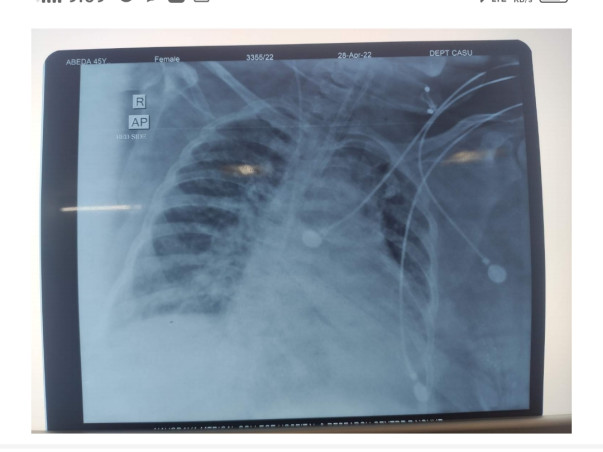

Abida Begum is 49 Years old Mumbai resident lives in dharavi. Suffering from severe lungs infection and not able to breathe without ventilator.

Ventilator and ICU is the key options for her recovery. She is admitted in a private hospital.

Ventilator and ICU is the key options for her recovery. She is admitted in a private hospital.